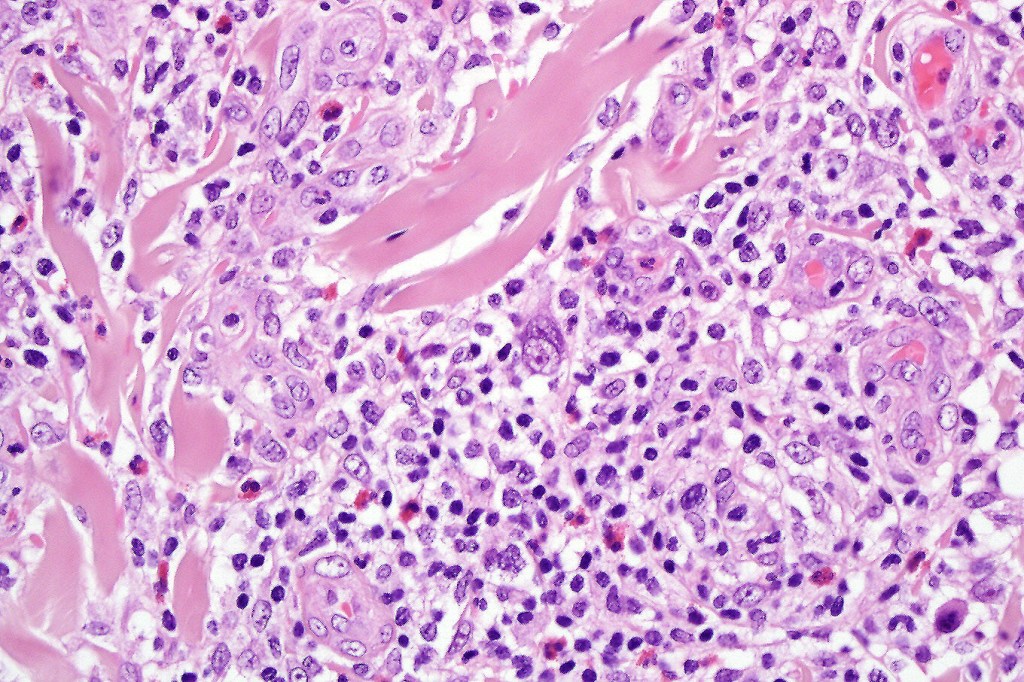

•Type A: 75-80%, wedge shaped infiltrate with base uppermost, large, anaplastic cells with abundant cytoplasm and vesicular nuclei containing prominent nucleoli, can resemble Reed-Sternberg cells, conspicuous mitoses & background infiltrate of lymphocytes, plasma cells, histiocytes, neutrophils & eosinophils

•Type C: 7-10% nodular infiltrate similar to primary cutaneous anaplastic large cell lymphoma